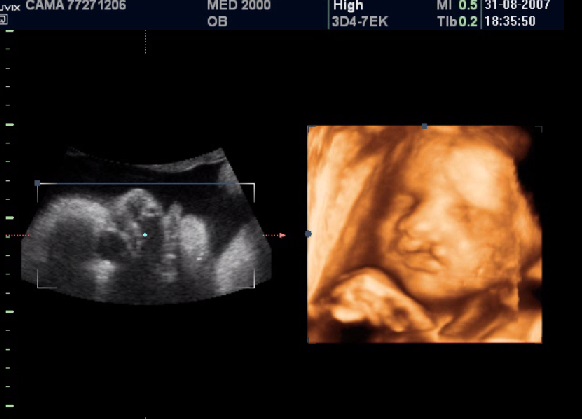

E’ una sindrome caratterizzata da anomalie a carico dell’orecchio (ipoplasia), microsomia emifacciale  e difetti della colonna vertebrale. La maggior parte dei casi sono sporadici ma esiste anche modalità di trasmissione autosomica dominante o autosomica recessiva.

-         anomalie facciali unilaterali (asimmetria, anoftalmia  e microftalmo unilaterali).

-         associazione di labioschisi e /o palatoschisi monolaterale con anomalie facciali unilaterali.

-         Anomalie del SNC: lipoma del corpo calloso, idrocefalia, malformazione di Chiari, encefalocele, ipoplasia del verme cerebellare, megacisterna magna, ipoplasia unilaterale del cervelletto.